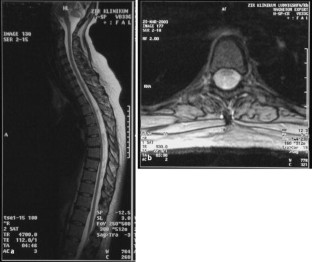

Abb. 2